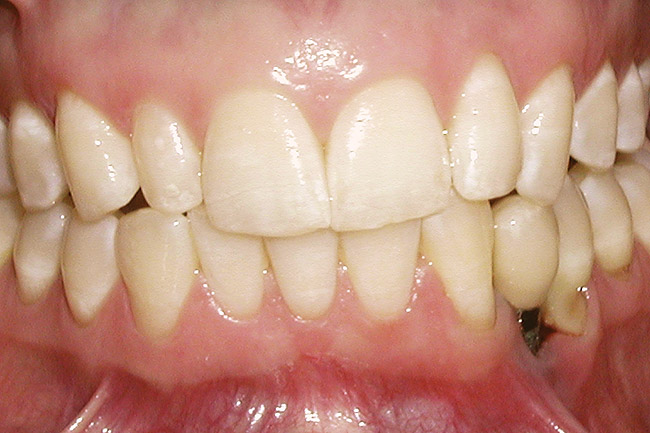

Figure 2  A preoperative retracted anterior view of the failing implant in the site of tooth No. 22.

Figure 2

A 28-year-old Caucasian female presented to the periodontist with a complaint of a mobile implant in the site of tooth No. 22 (Figure 2 and Figure 3). The patient had a congenitally missing tooth No. 23. No. 22 had erupted into site No. 23, leaving a vacancy at site No. 22, and was the reason for the original implant at site No. 22.